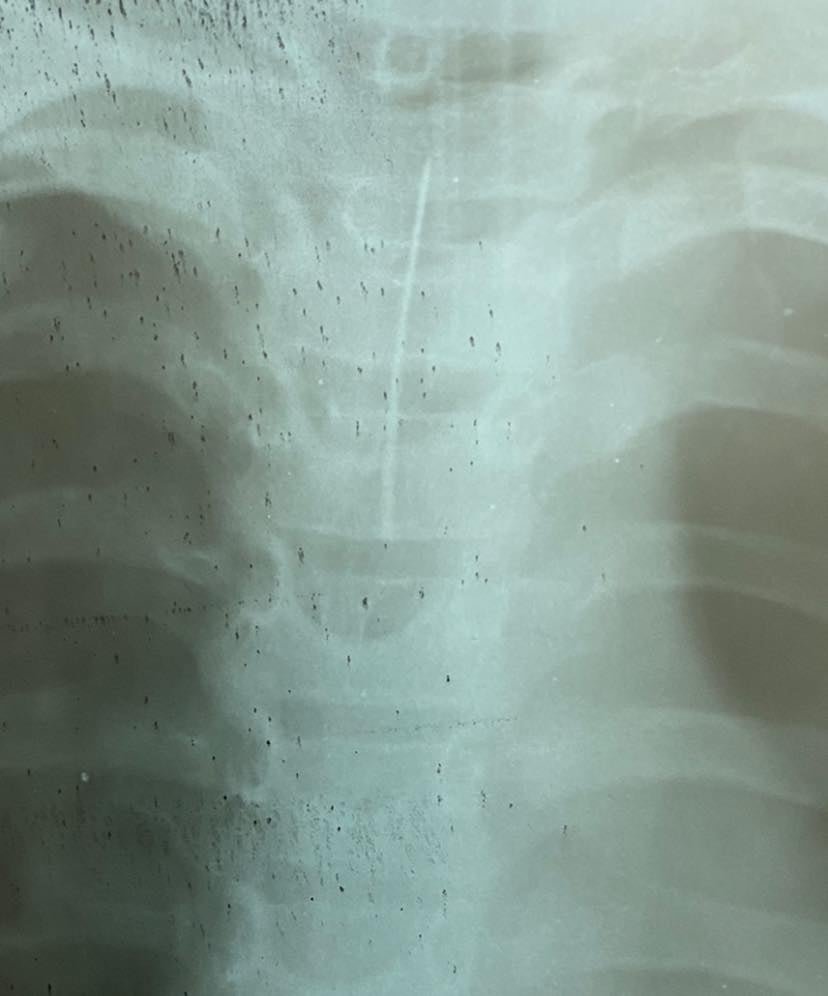

В Черкассах 9-летний школьник играл дома и положил иглу на язык, забыл и проглотил её. Родители быстро отреагировали и сразу же отвезли ребенка в больницу, врачам удалось спасти жизнь мальчику.

«Плюс одна спасённая маленькая жизнь на счету нашей команды. Специалисты хирургического, приёмного и анастезиологического отделения достали иголку из дыхательных путей ребёнка», — рассказали в больнице.

Команда врачей и медсестер сработала оперативно, поэтому всё прошло успешно. Как рассказал заведующий хирургической больницы Анатолий Шкляр Укринформу, родители не стучали мальчику по спине, а сразу повезли в больницу.

«Мы сразу развернули бронхоскоп и достали иглу», – отметил Шкляр.